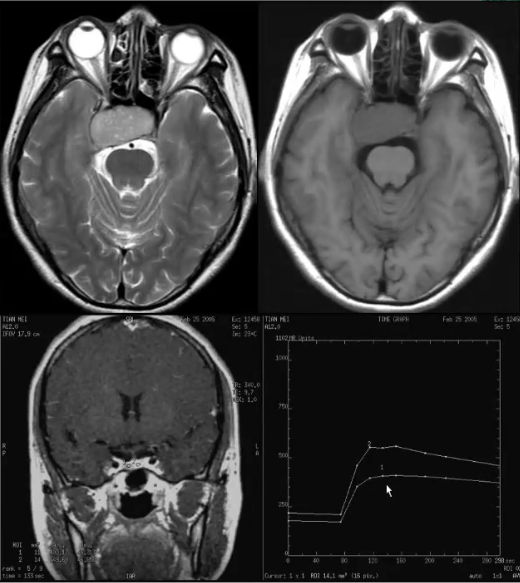

1)平扫:T1WI呈稍低信号,T2WI呈等或高信号

2)动态增强:呈缓慢低于正常垂体组织的强化。为渐进型强化曲线

垂体微腺瘤卒中